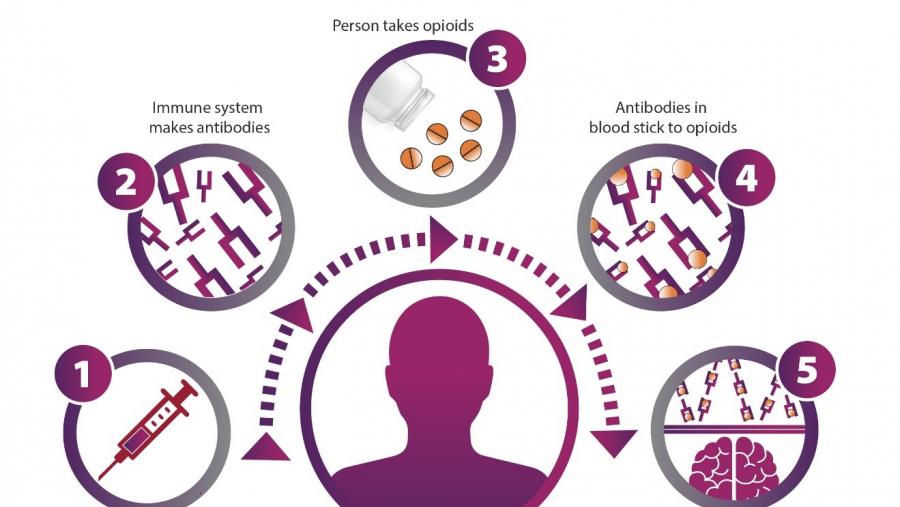

Human cell model mimics breathing center shut down by overdose

Published: October 11, 2023

Topics:

New Drugs/Screening Tools